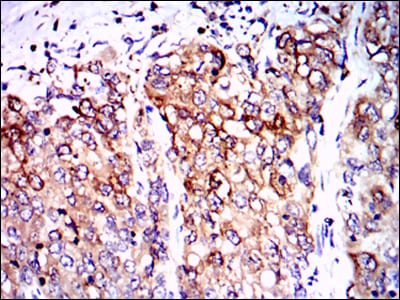

Immunohistochemical analysis of paraffin-embedded human cervical cancer tissues using PPP2R4 mouse mAb with DAB staining.

Immunohistochemical analysis of paraffin-embedded human lung cancer tissues using PPP2R4 mouse mAb with DAB staining.